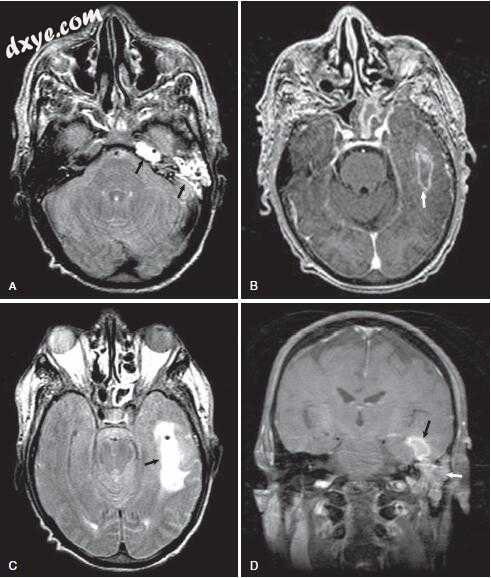

图-11. 影像学表现为左侧岩尖炎。 A,颞骨骨骼计算机断层扫描显示左颞骨岩尖炎。注意岩骨顶端的浑浊与骨质隔膜(星号)的破坏。在这个对比研究中也可以看到颈动脉管的裂开和岩骨颈动脉的狭窄(箭头)。 B,轴位非对比增强T1加权磁共振成像(MRI)显示乳突浑浊(星号)。与右侧看到的亮脂肪信号相比,左侧岩尖也是不透明的(箭头)。注意左侧颈内动脉狭窄口径(ICA;短箭头)与右侧ICA(箭头)相比。 C,轴向造影增强T1加权MRI在左侧岩尖处显示低信号,周边对比度增强(黑色箭头)与炎症一致。注意左侧ICA的窄口径(短箭头)与右侧的ICA(箭头)相比较。 D,冠状位造影增强T1加权MRI在左侧岩尖部显示低信号,周边对比度增强(黑色箭头)。注意增强毗邻岩尖的硬脑膜和颞叶(白色箭头)。 E,治疗前患者的MR血管造影(MRA)显示左侧岩石ICA变窄(箭头)。 F,随访MRA显示缩小后的ICA正常口径(箭头)。